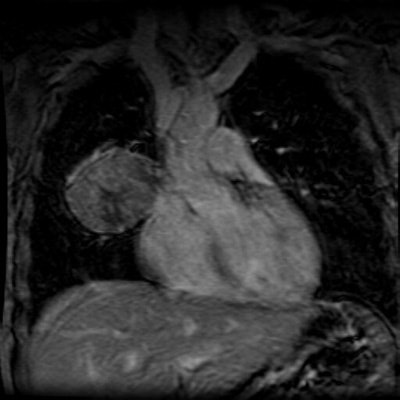

Post gadolinium images demonstrate the mass to enhance relatively homogeneously, but note that the area of necrosis does not enhance: